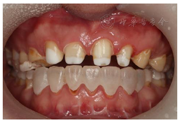

(1)面部检查:面部外形不对称,颏部居中,两侧口角高度不一致,面下1/3高度减小,两侧颧弓突度一致,下颌前突。中位笑线,上唇长度适中(图1)。(2)关节检查:颞颌关节:弹响(-),杂音(-),疼痛(-)。开口度正常,开口型有偏斜,肌肉触诊压痛:右侧上颌结节(+)、左侧上颌结节(++)、双侧翼内肌(+),其他肌肉及颞下颌关节区未诉异常,关节载荷实验无任何紧张和疼痛不适。(3)口内检查:上下颌牙中线较面中线向右偏斜,前后牙广泛不均匀磨耗,前牙磨耗后呈刃状;14、21、22、23及下颌牙唇颊侧颈部见釉质缺损,部分牙本质暴露,呈黄褐色,少量白垩色;44牙见开髓孔,表面暂封。12缺失,缺失牙间隙无。全口牙龈色形质未见异常,11牙、21牙唇侧牙龈龈缘高度不一致,21牙较11牙龈缘高约3mm。全口口腔卫生状况良好,菌斑、软垢少量,未及牙石及牙周袋。咬合检查:11-14牙与对颌牙反

下颌前突伴上下颌牙中线偏斜;前牙反颌;上颌牙列缺损;牙过度磨耗;釉质发育不全;44牙牙体缺损。

建议患者:(1)行正颌手术,上下颌骨前份根尖下截骨术,拔除24、34、44牙,改善颌间关系及下颌前突,提供修复空间;(2)前牙行牙周手术,使龈边缘协调对称;(3)上述治疗后,前牙固定修复,恢复牙体形态和功能。

与患者充分沟通,患者决定不做正畸治疗及牙周手术,选择行正颌手术,并在术后行全口咬合重建。因前牙釉质剥脱、牙冠磨耗短小,可利用牙釉质粘接面过小,需根管治疗后桩核冠修复。患者知情同意。